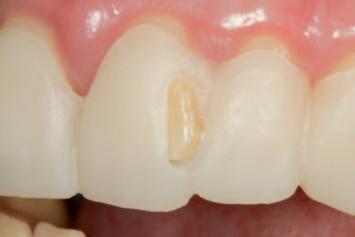

n On the basis of a facially driven smile design, with a patient-centred outcome in mind, contours of the underlying dentition that will impede the achievement of an idealised prosthodontic outcome are identified (Figure 1A) and planned for preparation with a custom digitally designed tooth reduction guide (Figure 1B). This guide is fabricated in a flexible, machinable polycarbonate material (Temp Premium Flexible, Zirkonzahn Srl, Gais, Italy) (Figure 1C).

FIGURE 1: Starting with the end goal in mind, a facially driven digital smile design reveals that the underlying tilting, drifting, rotations and maxillo-mandibular relations of the natural dentition will preclude the development of harmoniously contoured definitive restorations. A tooth preparation guide may be designed and milled at this early stage to assist in conservatively eliminating anticipated interferences, in a highly controlled workflow.

A C B

FIGURE 2: Initial seating of the preparation guide on the dentition allows the clinician to visualise the intended outcome of this treatment step.